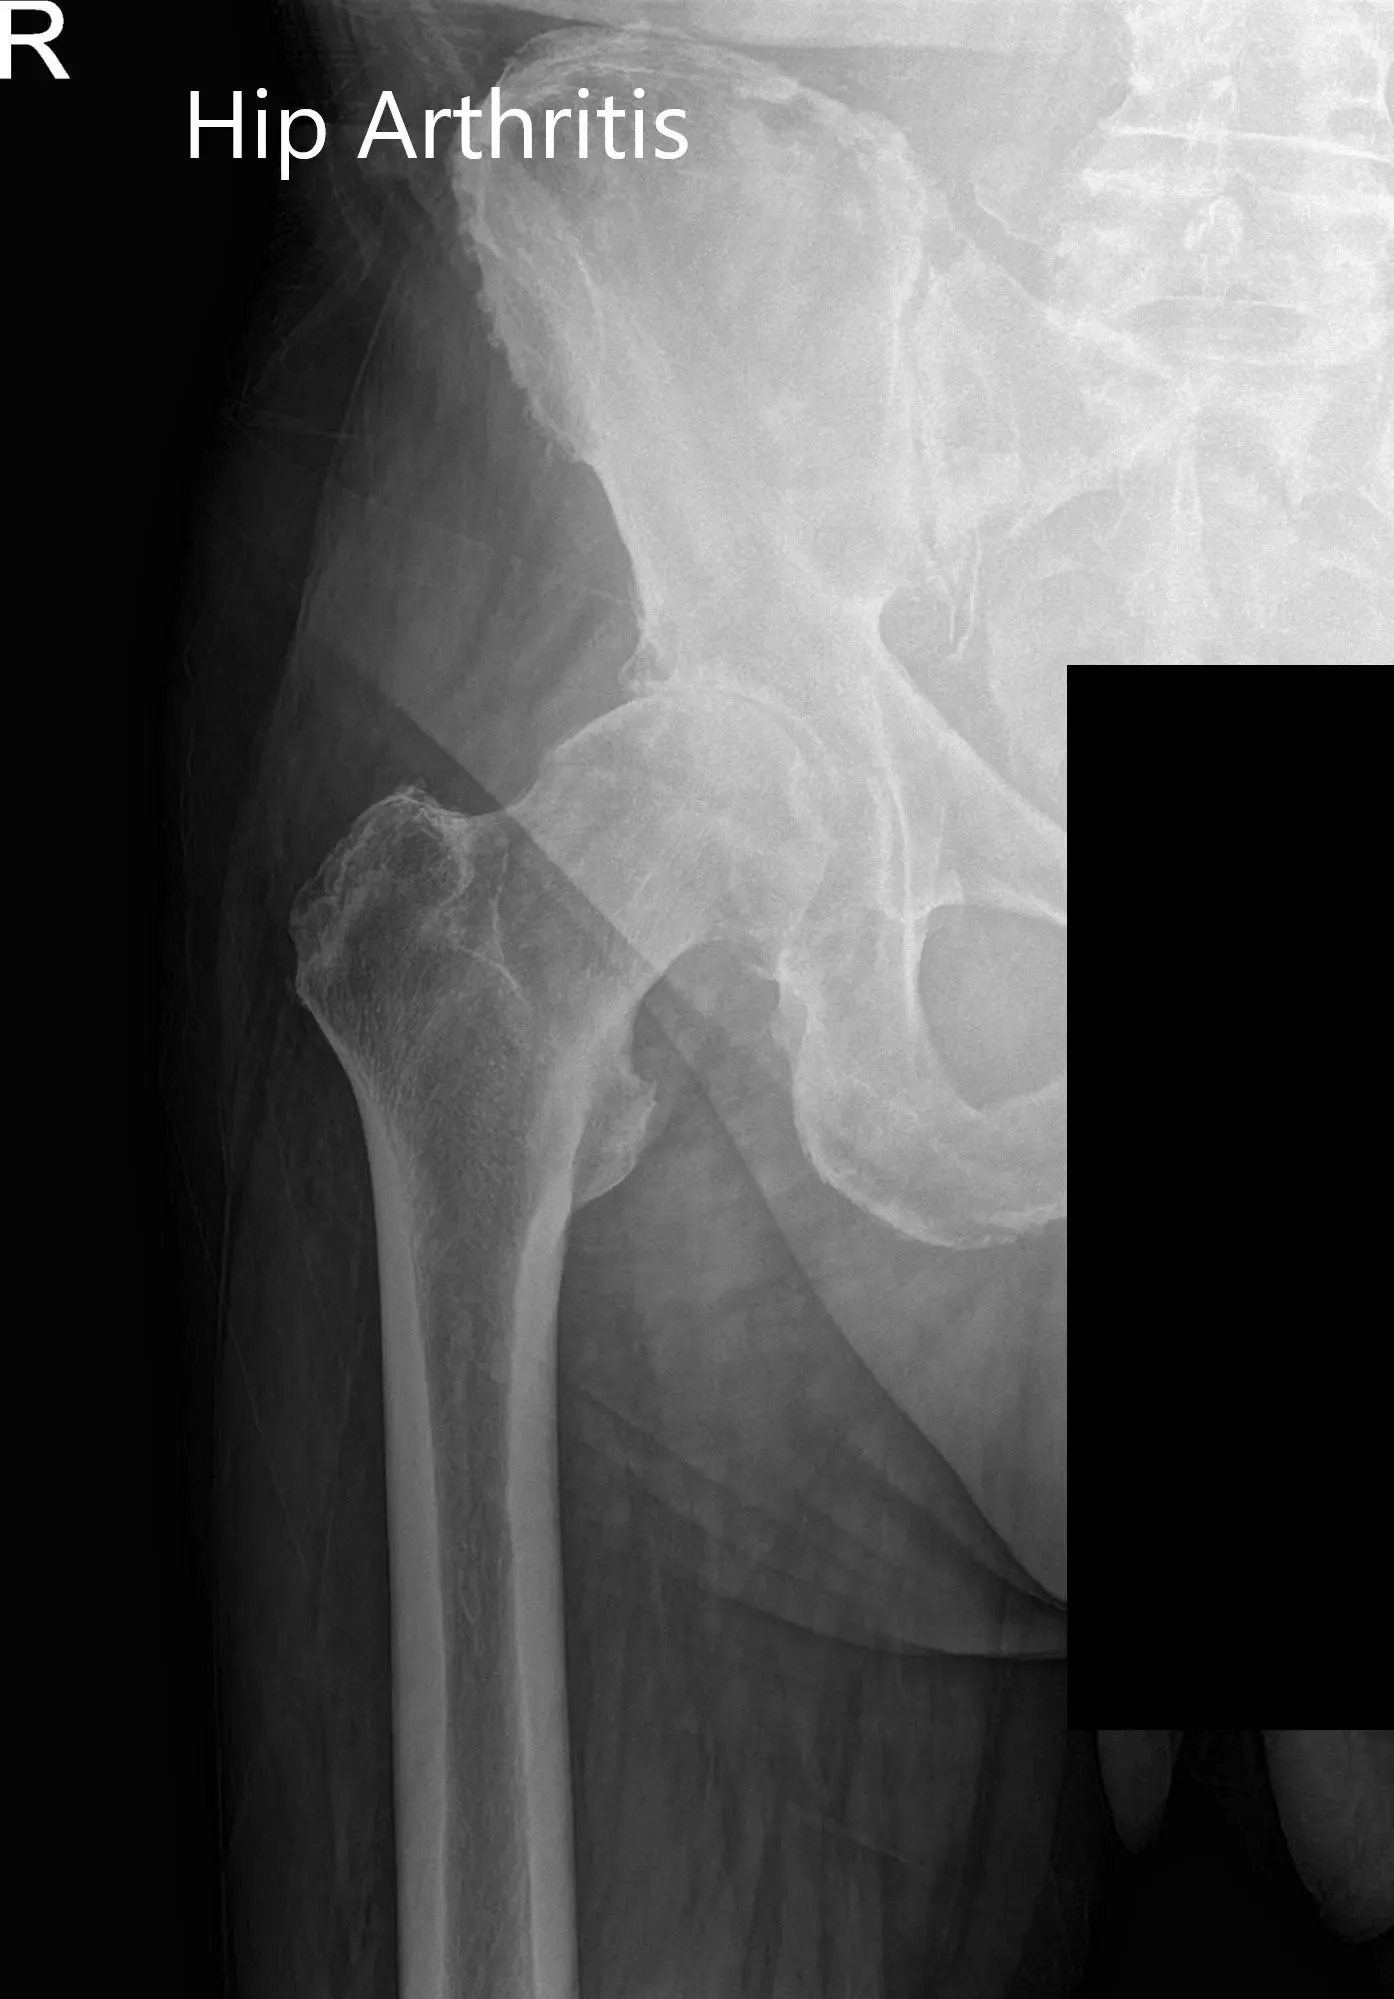

Las radiografías de la pelvis revelaron cambios osteoartríticos en la cadera derecha. Teniendo en cuenta sus comorbilidades y el dolor de cadera que limitaba el estilo de vida, le recomendaron una cirugía de reemplazo total de cadera. Se le informó del riesgo añadido de la cirugía debido a la fibrilación auricular y la hipertensión.

Imágenes de rayos X preoperatorias que muestran la visión lateral de la pata de rana y la pata de rana de la cadera derecha